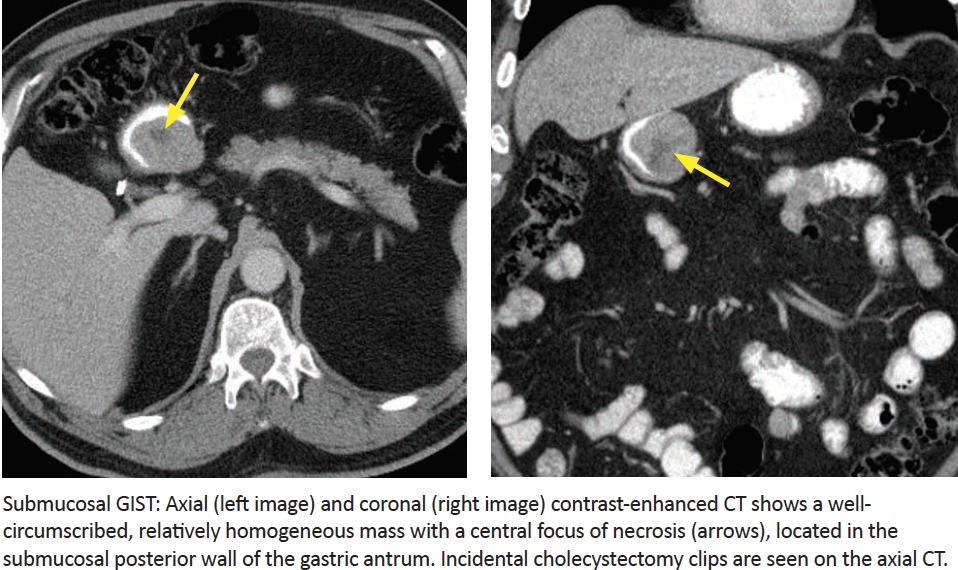

Gastrointestinal Stromal Tumor (GIST)

Imaging?